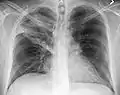

AP CXR showing right lower lobe pneumonia